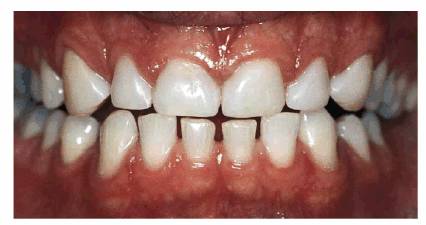

PROBLEM: This 60-year-old airline travel agent presented with a large

diastema of the maxillary central incisors (see Figures 23-10A, and 23-10E). Advanced cervical erosion was

Figure 23-10A: This 60-year-old woman presented with a large diastema between her central incisors and cervical erosion on her maxillary anterior teeth.